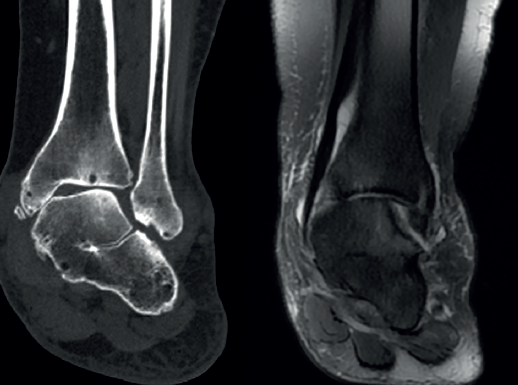

Con la llegada de pruebas avanzadas de imagen aumentó la estimación respecto a la población general. A partir de estudios con TC y disección en cadáveres se han publicado incidencias del 12-13%(29,30), cifras que son similares al 11% encontrado en un trabajo de coaliciones halladas en RM(31).

Sin un dato claro y con limitaciones sobre sesgos de selección reconocidos en muchos de esos trabajos, la bibliografía se ha decantado más por la predominancia de la CE, aunque quizás se deba a una mayor dificultad para reconocer una AC en las radiografías simples y en la RM(31).

Rozansky(41) y Lim(42) propusieron, solo para la coalición AC, una clasificación basada en imágenes 3D de TC. Ambos se basaron en la morfología de inclinación de la interlínea y la naturaleza del tejido (fibrocartilaginoso u óseo), pero Lim añadió la presencia de fractura con edema óseo asociando criterios de RM. Yun(43) también hizo uso de la TC y la RM para describir diferentes tipos de coalición AC según su localización y la presencia o no del os sustentaculi, que se sitúa entre el borde más posterior del sustentaculum tali y la prominencia más posteromedial del astrágalo. Por último, Wang(44) ha propuesto una excelente clasificación para describir la morfología de la coalición, según el hueso protagonista (sobrecrecimiento del astrágalo o del calcáneo, de ambos o con osículo intermedio), en función también de su condición fibrocartilaginosa u ósea, así como de la afectación sea de la subastragalina media, la posterior o de ambas.